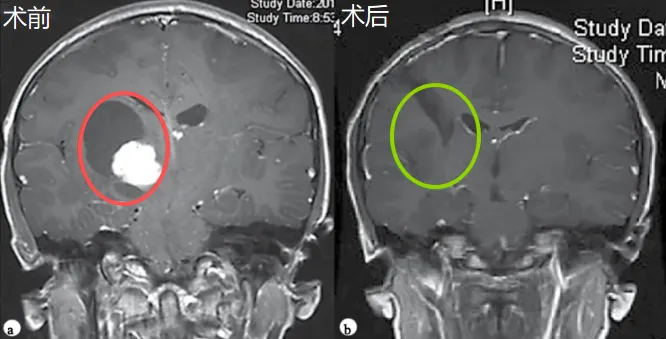

术前(红色标示)与术后(绿色标示)影像对比显示肿瘤全切,脑组织复位,无脑出血、脑水肿等损伤。